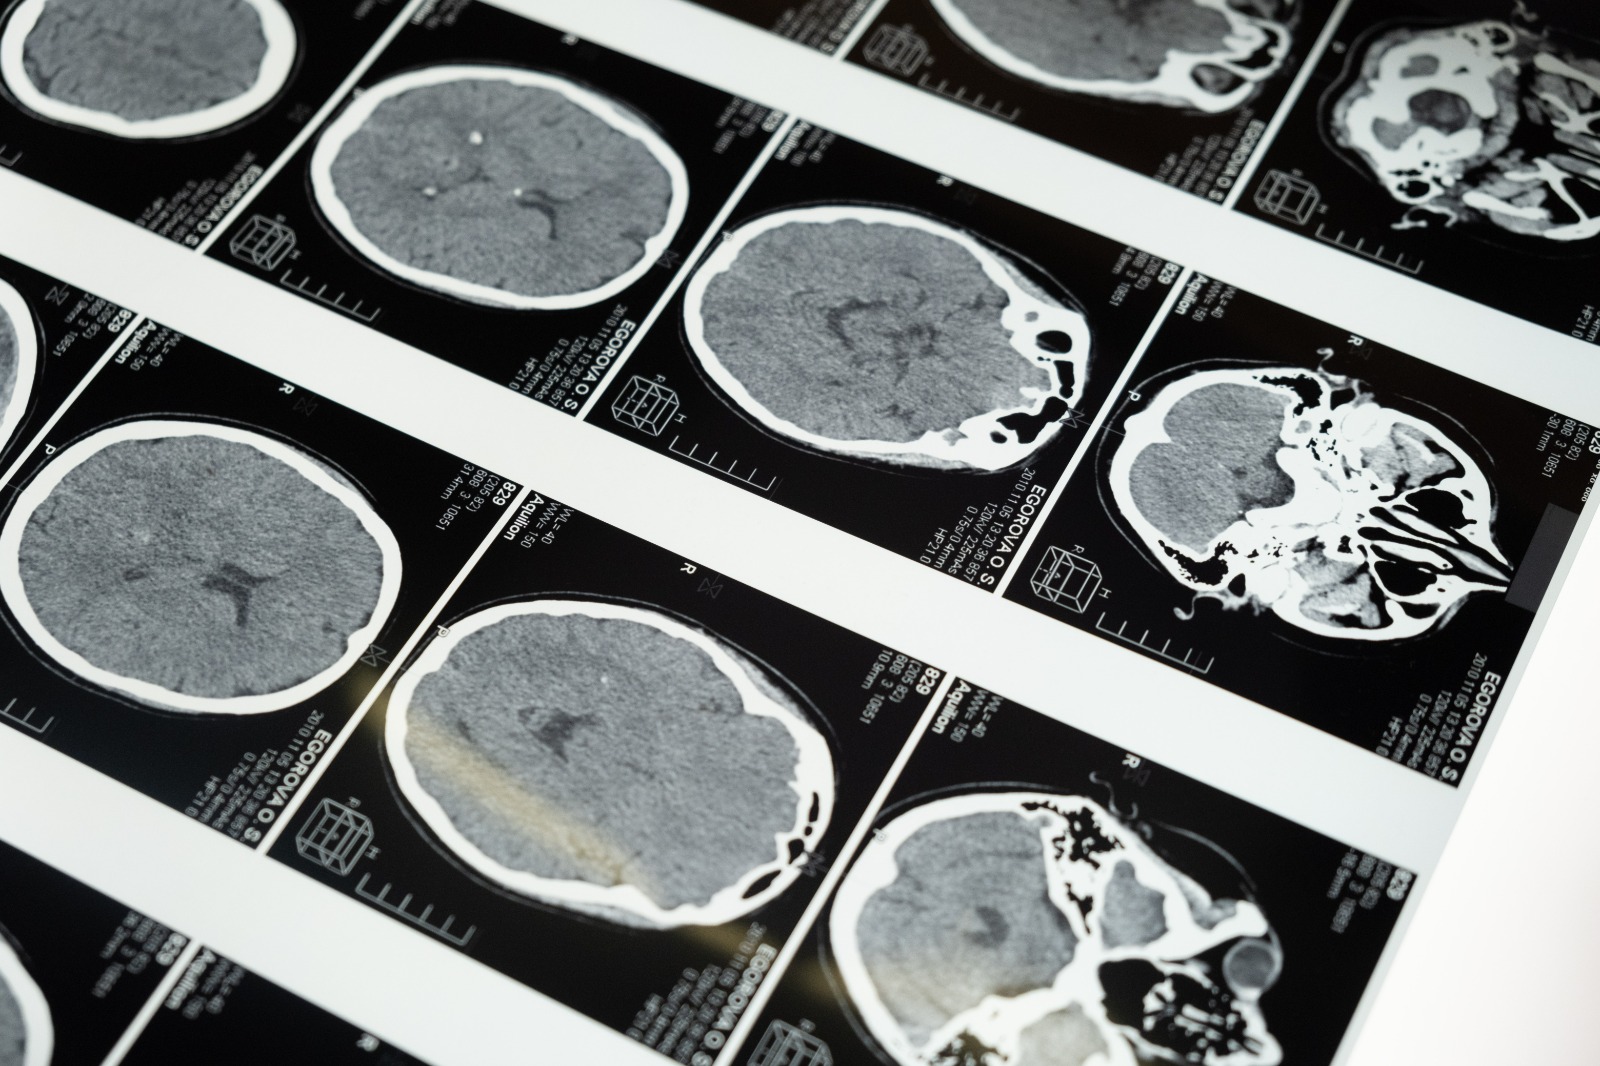

Beyin zarlarının ileri derecede iltihaplanması sonucu meydana gelen bir hastalıktır. Hastalığın etkeni virüsler, bakteriler ve parazitler olabilir.

Menenjit, meninksin (beyni ve omuriliği örten zarlar) iltihaplanmasıdır. Çoğunlukla vücudun başka bir bölgesindeki enfeksiyondan tipik olarak kan dolaşımı yoluyla meninkse ulaşan mikroorganizmaların yol açtığı enfeksiyon sonucu oluşur. Doktorunuz omurilik sıvısından aldığı örneği inceleyerek menenjit tanısı koyabilir. Bebeklerde ve genç çocuklarda belirtileri saptamak zor olabilir.